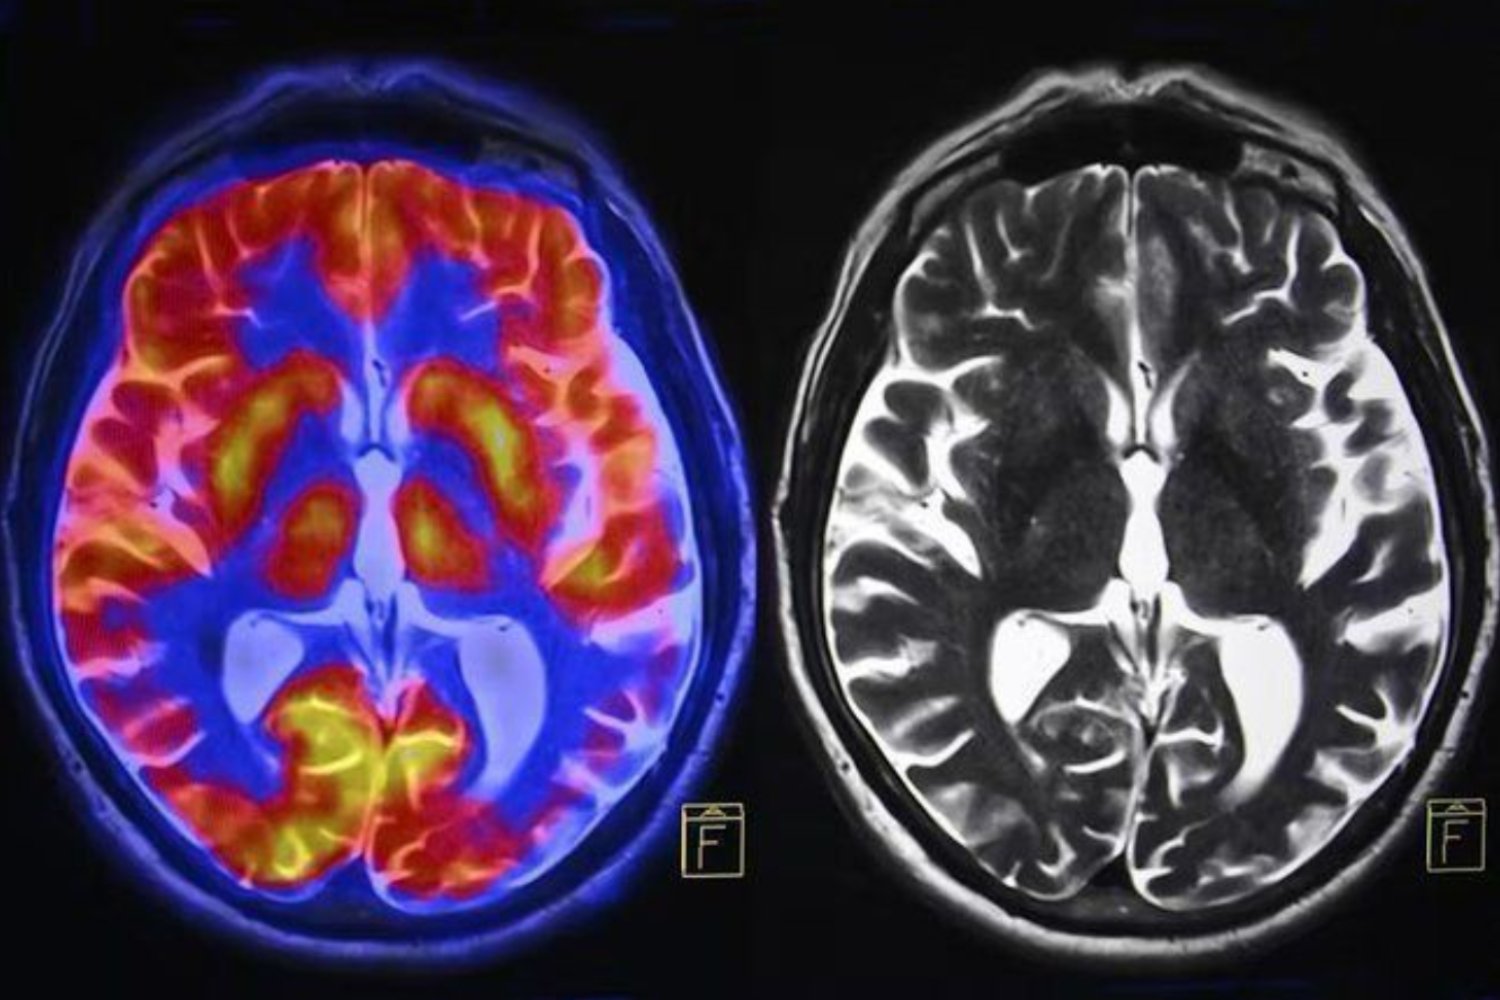

Según McDonald, el mayor obstáculo para cambiar es un desajuste entre quién queremos ser y la identidad que el cerebro da por válida. La llamada “red neuronal por defecto” —que sostiene nuestra narrativa interna— actúa como un filtro que determina lo que creemos posible. Si la identidad actual no coincide con el objetivo, el cerebro boicoteará el avance. Por ello, recomienda adoptar la identidad de la persona que ya logró lo que buscamos: escribir como escritor, actuar como emprendedor, tomar decisiones como un líder.